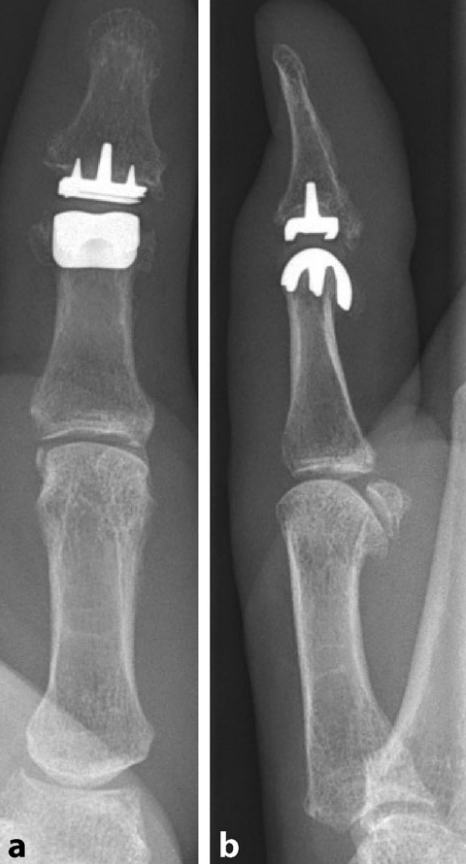

若关节囊韧带复合体发生慢性损伤,可导致关节不稳定及退行性变。对于症状性患者,拇指末节关节融合术是有效选择,例如采用双螺纹螺钉固定于约20°功能位以恢复拇指功能。部分病例可选择表面置换假体作为保留关节活动度的替代方案(图3)。

图3. 拇指指间关节表面置换假体X线影像:a 正位片,b 侧位片